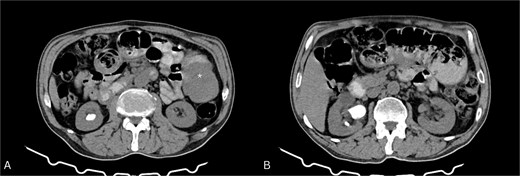

CT abdomen (Fig. 1) showed dilated ileal loops with mild–moderate wall thickening up to 5.7 cm and a 6 cm left-sided soft tissue mass, suggestive of partial small bowel obstruction secondary to neoplasm.

Contrast-enhanced CT of the abdomen. (A) Axial view showing a soft tissue mass-like lesion in the left abdomen (star). (B) Dilated bowel loops with mild to moderate thickening of the bowel wall.